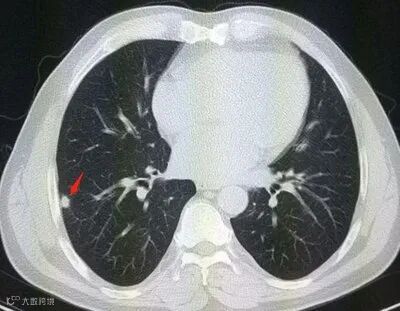

引起肺结节的原因有很多,感染、炎症、肺部原发肿瘤、转移瘤以及其他良性疾病,都可能会表现为肺结节。

临床观察发现,经CT筛查发现的肺结节,90%以上都是良性的,真正恶性的比例只有1.2%。

若在随访过程中,出现结节增大、结节密度增大或实性成分增加等,要听从医生建议,进行进一步检查及处理。